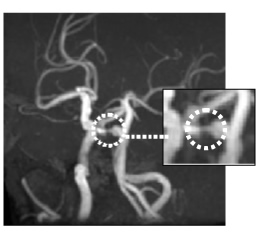

MRA画像

左内頸動脈狭窄

MRA画像

脳動脈瘤